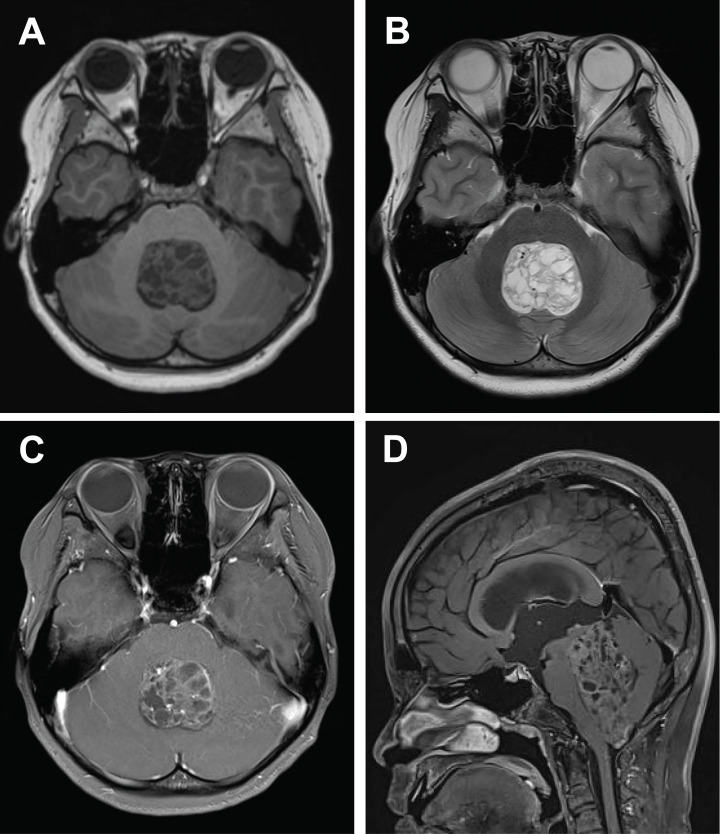

伴有BCL6协同抑制因子(BCOR)内串联重复(ITDs)的中枢神经系统肿瘤是一种罕见的儿科肿瘤,具有独特的分子和组织病理学特征。迄今为止,文献记录了69例,包括我们的机构病例。这些肿瘤主要发生在幼儿,小脑是最常见的解剖部位。放射学上,这些肿瘤表现为大的、界限清楚的肿块,常表现为坏死、出血和不均匀强化。组织学上,它们的特征是单形细胞群,具有室管膜瘤样血管周围假性结节,粘液样间质和有丝分裂活性升高。免疫组织化学,这些肿瘤表现出稀疏的胶质原纤维酸性蛋白表达,而vimentin和CD56的染色一致呈阳性。定义的分子标志是BCOR基因外显子15内的杂合ITD,插入长度从9到42个氨基酸不等。BCOR免疫组化在97.9%的检查病例中显示核阳性,尽管这一发现不是BCOR ITDs的病理特征。本综述综合了所有已发表的这种新型肿瘤病例的数据,提供了临床表现、神经影像学发现、组织病理学特征与鉴别诊断考虑、治疗方法和预后结果的详细分析。

Central nervous system tumors with BCL6 corepressor (BCOR) internal tandem duplications (ITDs) constitute a rare, recently characterized pediatric neoplasm with distinct molecular and histopathological features. To date, 69 cases have been documented in the literature, including our institutional case. These neoplasms predominantly occur in young children, with the cerebellum representing the most frequent anatomical location. Radiologically, these tumors present as large, well-circumscribed masses frequently demonstrating necrosis, hemorrhage, and heterogeneous enhancement. Histologically, they are characterized by a monomorphic cellular population featuring ependymoma-like perivascular pseudorosettes, myxoid stroma, and elevated mitotic activity. Immunohistochemically, these tumors exhibit sparse glial fibrillary acidic protein expression while consistently demonstrating positive staining for vimentin and CD56. The defining molecular hallmark is a heterozygous ITD within exon 15 of the BCOR gene, with insertions ranging from 9 to 42 amino acids in length. BCOR immunohistochemistry reveals nuclear positivity in 97.9% of examined cases, although this finding is not pathognomonic for BCOR ITDs. This comprehensive review synthesizes data from all published cases of this novel tumor entity, providing a detailed analysis of clinical presentation, neuroimaging findings, histopathological features with differential diagnostic considerations, therapeutic approaches, and prognostic outcomes.